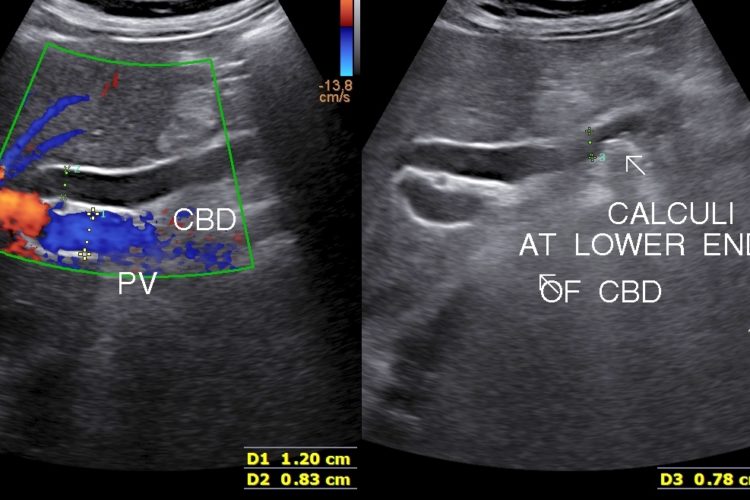

• Choleydocholithiasis (Calculus/ Calculi in Biliary tree): Passage of calculus/caculli in common bile duct leads to biliary colic, nousea, vomitting.

• Surgical jaundice and pancreatitis are complication.